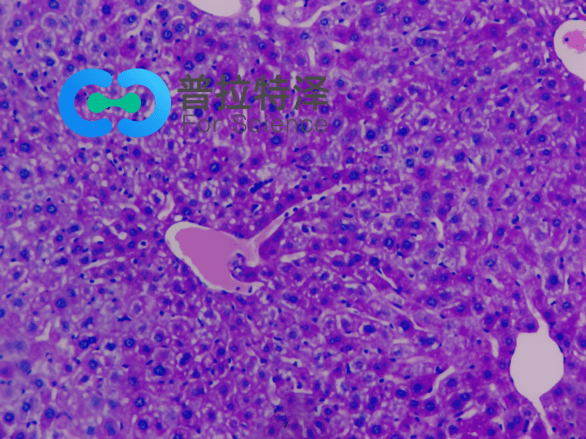

PAS染色法,全稱為過(guò)碘酸-雪夫染色法(Periodic Acid-Schiff stain)。在組織學(xué)上,主要用來(lái)檢測(cè)組織中的糖類。它利用過(guò)碘酸將糖類相鄰的兩個(gè)碳上的羥基氧化成醛基,再與Schiff試劑中的無(wú)色品紅結(jié)合,形成紅色物質(zhì),從而顯示糖原和其他多糖物質(zhì)在細(xì)胞內(nèi)的分布。